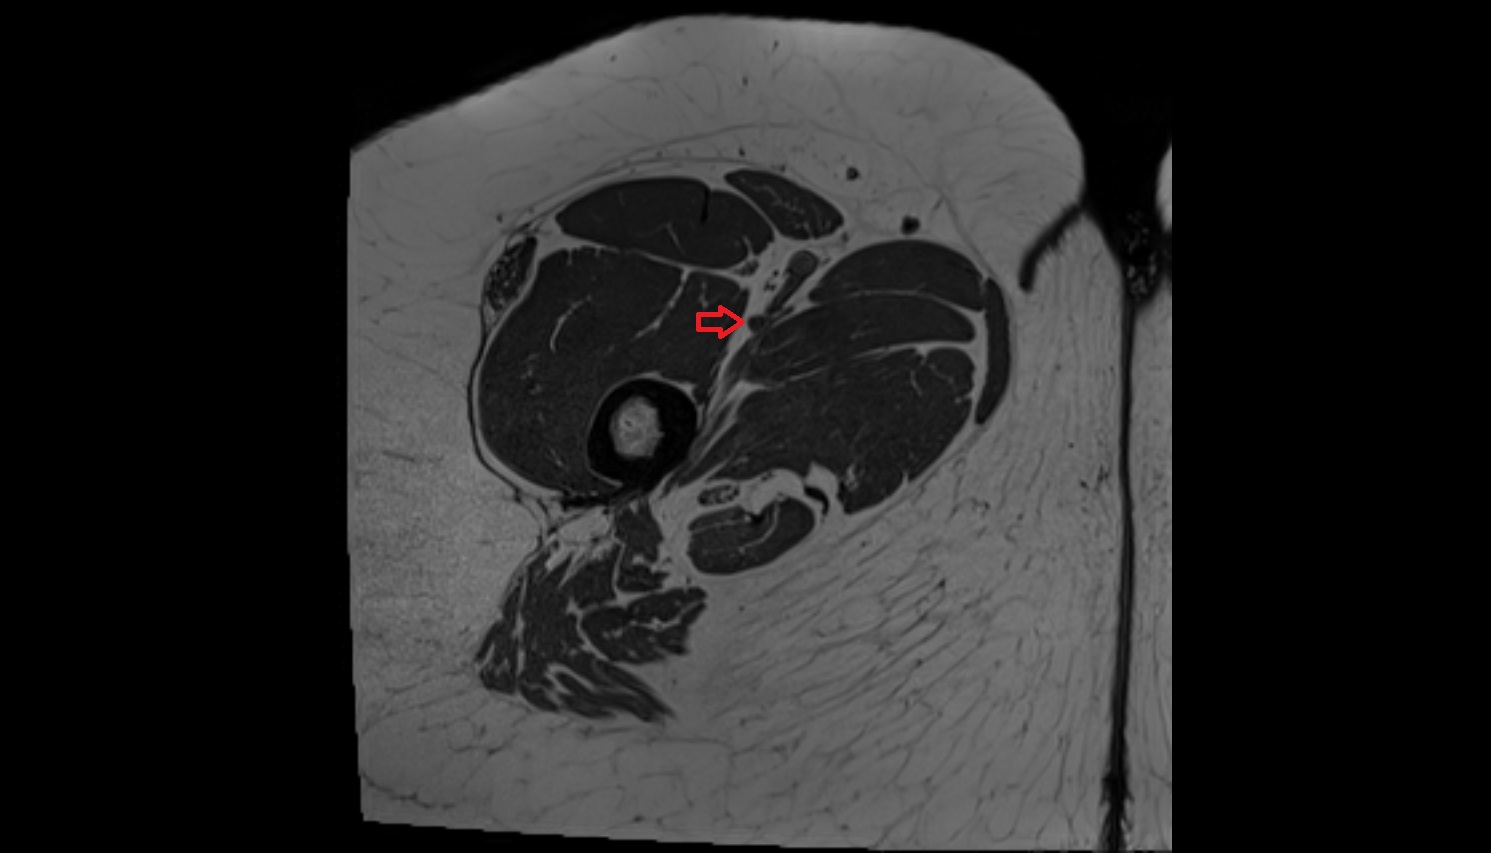

- Femoral artery

- Deep femoral artery (profunda femoris)

- Deep femoral vein (profunda femoris vein)

- Adductor magnus muscle

- Adductor longus muscle

- Sartorius muscle